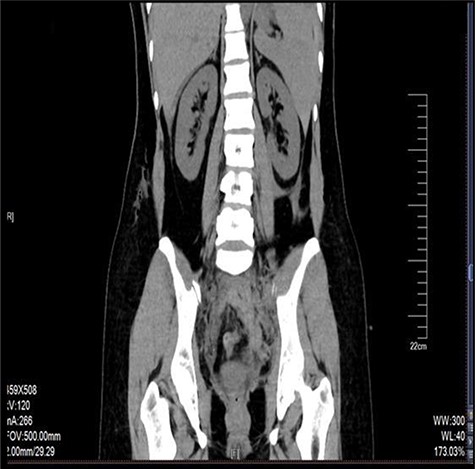

Laparoscopy revealed about 200 ml pelvic free fluid, there was no evidence of active bleeder from pelvic vessels, a retroperitoneal hematoma 6-7 cm in diameter up to the left iliac fossae down to 5 cm above the uterine rectal fossae (Fig. 1). The sigmoid colon and its mesenteric membrane are closely adhered to the left lower abdominal wall. The uterus is anterior full in shape and normal in size, the posterior wall of the uterus partly adhered to the rectum, the fallopian tubes are normal in shape.